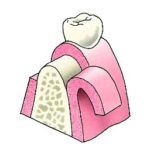

Tandheelkundige implantaten worden gebruikt om verloren tanden te vervangen. Ze zijn over het algemeen gemaakt van titanium, een metaal dat compatibel is met lichaamsweefsels en in staat is zich aan bot te binden.

Een tandheelkundig implantaat is in wezen een titaniumschroef of -cilinder, tussen 4 mm en 16 mm lang, die wordt ingebracht in een voorbereide holte in de kaak en fungeert als een vervangende wortel voor de ontbrekende tand of kies. Een speciale bevestiging, het abutment genaamd, wordt aan de bovenkant van het implantaat bevestigd en vormt de externe verbinding met de vervangende tand (kroon). Er zijn ook implantaten uit één stuk waarbij het abutment en het implantaat deel uitmaken van één stuk.

- Bij het ontbreken van één tand of kies, wordt een implantaat ter plaatse van het ontbrekende gebitselement in de kaak geplaatst en wordt daarop een kroon van keramiek of een combinatie van keramiek met metaal vastgezet..